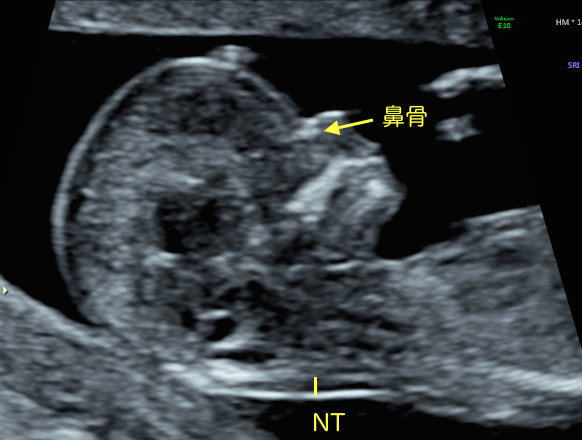

Nt エコー

先天異常部より Nt Nuchal Translucency について 医療者向け 日本産婦人科医会

Nt Nuchal Translucency ある産婦人科医のひとりごと

14 初期の超音波マーカー検査 日本産婦人科医会

先天異常部より Nt Nuchal Translucency について 医療者向け 日本産婦人科医会

妊娠初期超音波の出生前診断における役割 Fetal Skeletal Dysplasia Forum

02 妊娠初期 胎児の頸部浮腫 Nt 妊娠11 13週でcheck 深谷産婦人科 医学情報

胎児超音波ーマーカー検査とは ヒロクリニック

妊娠初期超音波の出生前診断における役割 Fetal Skeletal Dysplasia Forum

胎児の首の後ろのむくみ 浮腫 Nt とは 妊娠初期 All About

Nt Nuchal Translucency について 出生前検査 Nipt 遺伝カウンセリング 妊婦健診 エコー検査 産科 婦人科 産婦人科

胎児の首の後ろのむくみ 浮腫 Nt とは 妊娠初期 All About

胎児の首のむくみ Nt クリフム夫律子マタニティクリニック

Nt Nuchal Translucency ある産婦人科医のひとりごと

Nt Nuchal Translucency ある産婦人科医のひとりごと